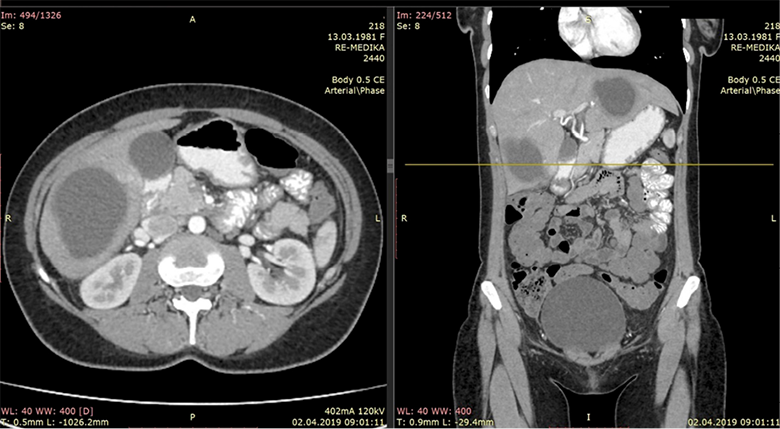

An CT scan of the abdomen was performed and were found two cystic liver formations, also a cystic formation was verified in the pelvis. The native series of the abdominal CT have shown a segment II and IV hepatic per-magna cystic formations with dimensions: No I: 80×60×74 mm (Figure 1) and No. II: 70×60×58 mm (Figure 2). The changes are with a pericystic reaction of a hypodense character. The formation in the second hepatic segment had a visible mass effect on the stomach. In post contrast series, cystic liver formations were shown as hypodense, hypovascular structures with a clearly expressed contrast accumulation in the cystic membrane and with a demarcation of the pericystic reaction. Per magna cystic formation with hypodense character was also detected at the level of the small pelvis, retrouterine, in the Douglas space, with dimensions of 93×90×62 mm (Figure 3). The cyst has a clearly expressed mass effect on surrounding organ structures. Utter in the AVF pressed to the left. The liver cystic formations were with characteristics of Ehcinococcal cyst but with no serological verification.

Figure 2. Segment IV hepatic cystic formation

Figure 3. Hypodense cystic formation in small pelvis